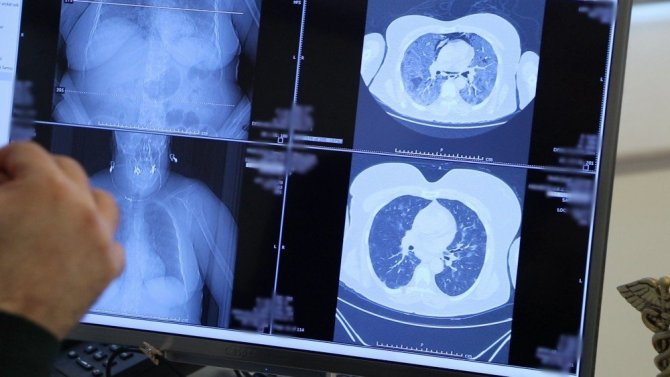

İngiltere'de korona virüsün mutasyona uğramış hali tespit edildi. VM Medical Park Samsun Hastanesi'nde görev yapan ve şu ana kadar binlerce korona virüs hastasının şifa bulmasını sağlayan Göğüs Hastalıkları Uzmanı Prof. Şevket Özkaya, mutasyona uğramış virüs hakkında açıklamalarda bulunarak korona virüsü ağır geçirmiş bir evli çiftin akciğerleri üzerinden örnekler verdi. Çocuklarından korona virüs bulaştığı öğrenilen evli çiftin ilk iki gün hafif seyredilen hastalıklarının birkaç gün içinde yaygın solunum yetmezliğine dönüştüğü belirlendi. İncelediği akciğerlerin ve verdiği vaka örneğinde direkt temasın, bulaşıcılığı ve hastalığı çok hızlı ilerlettiğini gösterdiğine dikkat çeken Prof. Dr. Şevket Özkaya, "Örnek vermek gerekirse, bir karı-kocanın çocuklarının ikisi de pozitif olan ama genç oldukları için akciğerleri tutulmamış ama genç-taşıyıcı olduğu için anne ve babalarına bulaştıran aile içindeki gözlemlenen vakayı size paylaşacağım. Bu kadın hastamızda, kızından aldığı virüs nedeniyle oluşan çok hafif pulmoner akciğer tutulumu şikâyeti birkaç gün içerisinde hızla ilerliyor ve yaygın solunum yetmezliği ortaya çıkıyor. Bu vaka, direkt temasın çok hızlı bulaşıcılığını ve hastalığın çok hızlı ilerlediğini gösteriyor. Hastamızın eşine baktığımızda da yine kızından bulaşan virüsle akciğerinde hafif bir tutulma olduktan sonra çok hızlı bir şekilde ilerleyip hastaneye yatacak düzeyde bir nefes darlığı ortaya çıktığını gördük. Halkın mutasyona uğrayan korona virüsüyle ilgili bilmesi gereken iki nokta var. Birincisi mutasyonlu virüs çok hızlı şekilde bulaşabilir, çünkü bulaştırıcılığı çok fazla. İkincisi de tedaviye rağmen düzelme görülemeyebilir ama bu mutasyon olduğunu göstermez" diye konuştu.